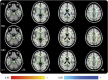

Results: Acutely, increased axial diffusivity drove a fractional anisotropy (FA) increase, while decreased radial diffusivity drove a negative regression between FA and Verbal Letter Fluency across widespread white matter regions, but particularly in the ascending fibers of the corpus callosum. Raised FA is hypothesized to be caused by astrogliosis and compaction of axonal neurofilament, which would also affect cognitive functioning. Chronically, FA was decreased, suggesting myelin sheath disintegration, but still regressed negatively with Verbal Letter Fluency in the anterior forceps.

Conclusions: Acute mild/moderate traumatic brain injury is characterized by increased tissue FA, which represents a clear neurobiological link between cognitive dysfunction and white matter injury after mild/moderate injury.